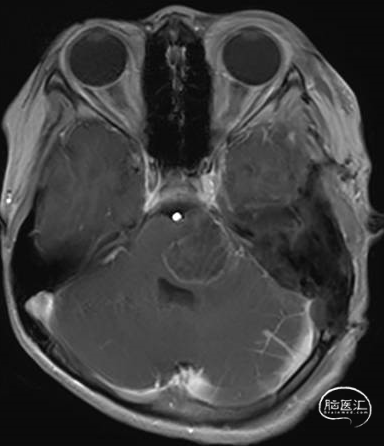

术前MRI

术后MRI